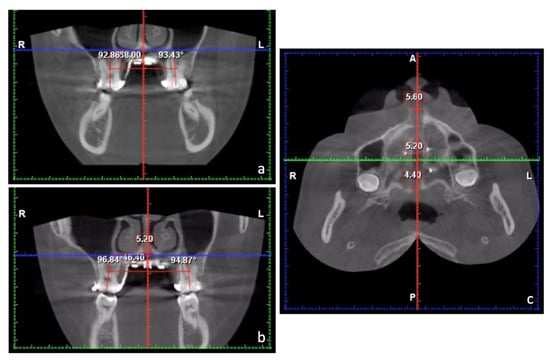

| JR-JL | 82.2 mm |

|---|---|

| AG-GA | 117.7 mm |

| Maxillomandibular transverse discrepancy | 35.5 mm |

| Expected transverse difference (14 y/o) | 18 mm |

| Maxillomandibular transverse differential index | 17.5 mm |